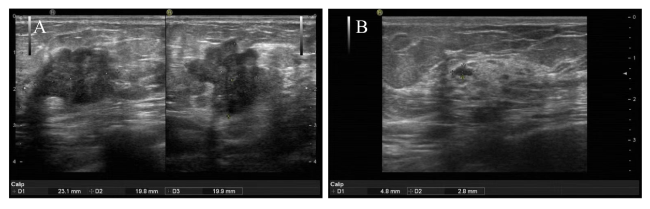

图2 一例联合模型预测乳腺癌NAC患者pCR

注:A为NAC前乳腺癌病灶,B为NAC 3个周期后乳腺癌病灶;患者女,55岁,NAC前病灶大小约23.1 mm×19.8 mm×19.9 mm,联合模型预测达到pCR概率为0.857,在接受NAC 3个周期后,病灶大小4.8 mm×2.8 mm,达到pCR。

Figure 2 Joint model for predicting pathological complete response in one case of breast cancer patient after neoadjuvant chemotherapy